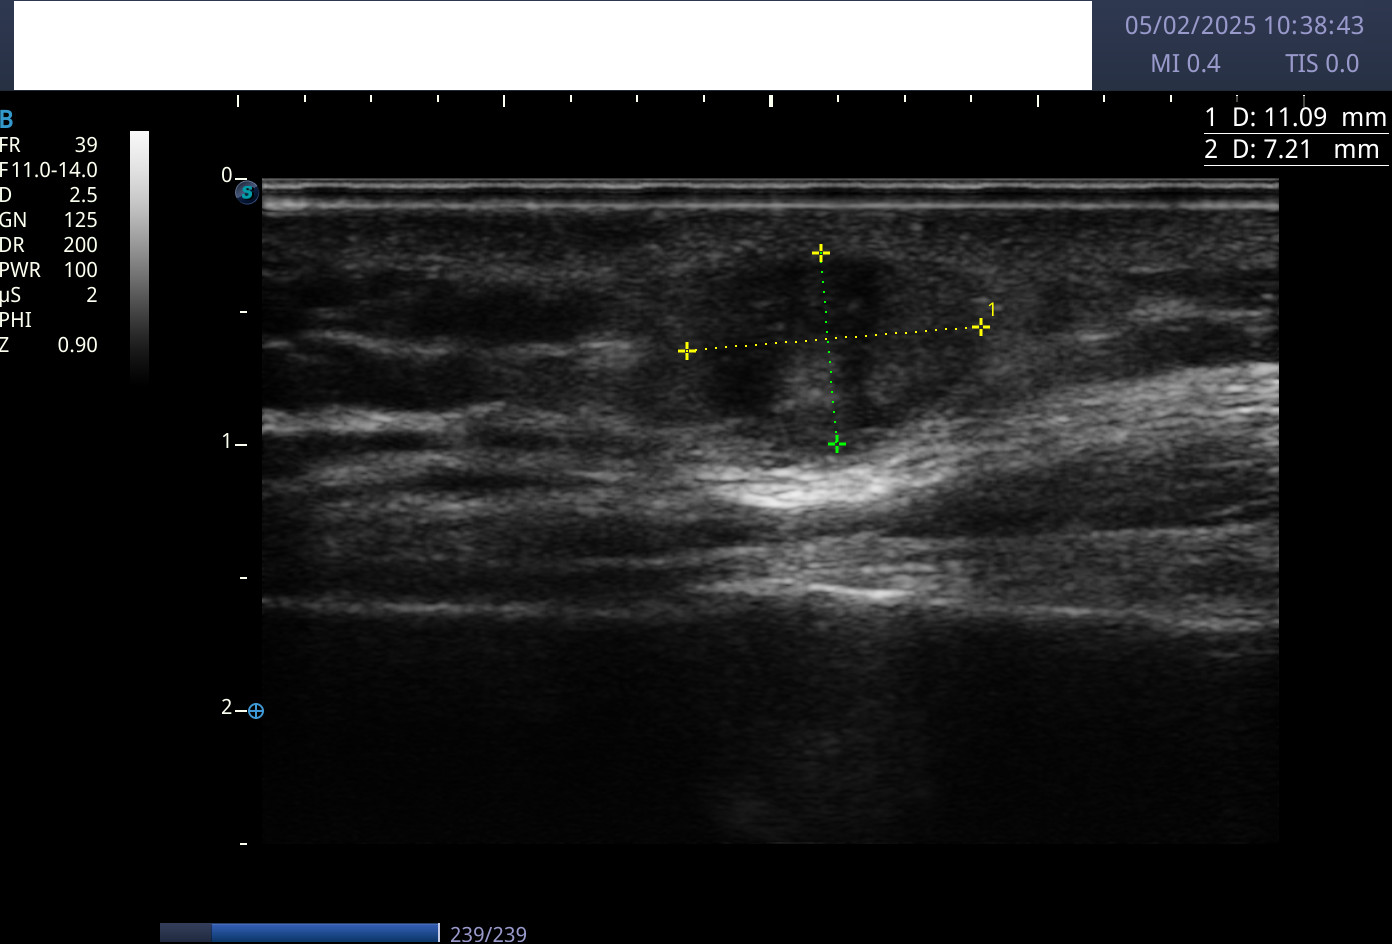

Hallazgos ecográficos

En la ecografía se apreciaron lesiones hipoecogénicas a nivel de plano subcutáneo con bordes mal definidos, sin actividad Doppler.